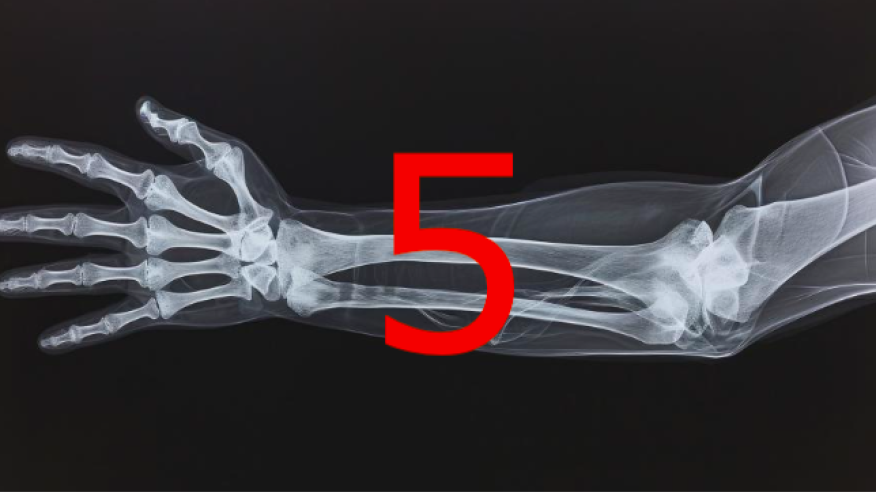

5 Fractures You Don’t Want to Miss Save

In orthopedic practice, missing the wrong fracture can significantly alter a patient’s outcome. Certain injuries may appear subtle on initial imaging yet carry serious consequences if not promptly recognized and managed. Below are five fractures that warrant a high index of suspicion due to their risk of displacement, nonunion, or long‑term degenerative change.